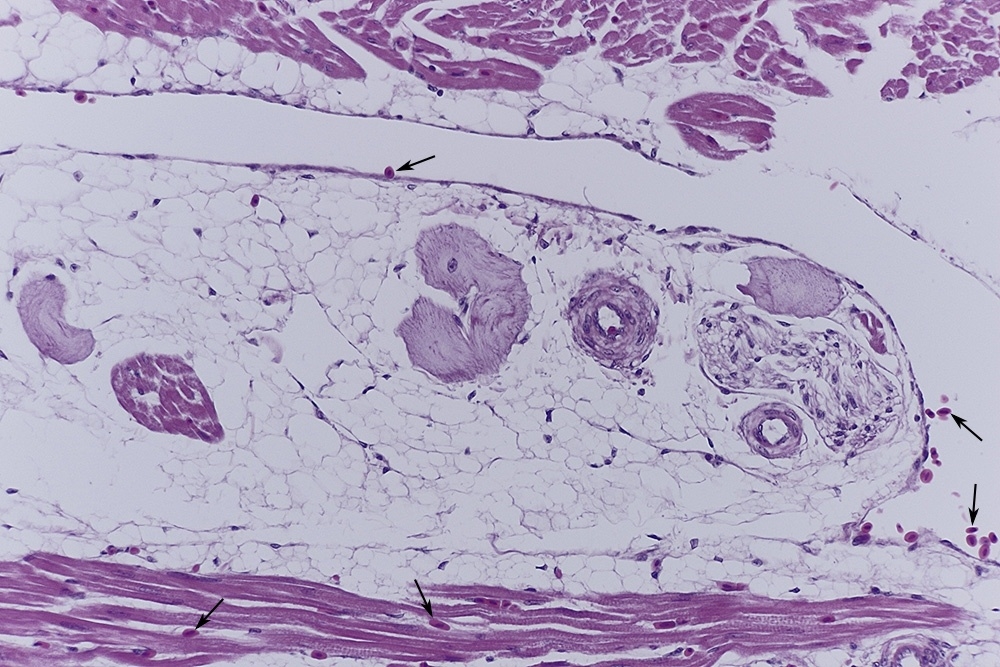

Die Purkinje-Fasern als spezialisierte Herzmuskelzellen, bilden den letzten Teil der

Impulsleitung mit direktem Übergang in die Myocardzellen.

Diese, oft als ,,Möpse" beschriebenen Zellen, liegen im Inneren der Herzkammern

zwischen Endocard und Myocard in einer Schicht aus lockerem Bindegewebe zusammen

kleinen Blutgefäßen und nicht myelinisierten Nerven.

Abb.2: Purkinjefasern 1, Endocard 2

Abb.3

Abb.4

Abb.5

Abb.6

Ich habe dein Bild 3 mal mit Pfeilen versorgt. Was sind das für welche Zellen? Weil die im Gewebe und auch im Lumen vorkommen vermute ich größere Erythrozyten die bei Vogel ja ein kern haben. Stimmt das?

Auch muss man beachten, dass die Erythrozyten beim Vogel kernhaltig sind.

Ja, und du hast Recht, es sind kernhaltige Erythrozyten.